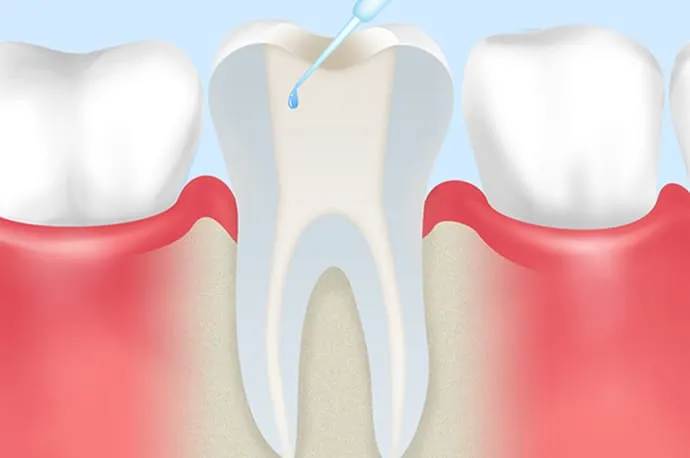

③根管貼薬

根管拡大と洗浄後、根管内にお薬を入れて一時的に封鎖します。これは、処置だけでは取りきれなかった細菌をさらに減らすことを目的としています。

根管貼薬(1回目治療終了)

ある程度消毒が完了した段階で、根管内にお薬を入れてフタをします(根管貼薬)。この状態で一度治療を終え、1~2週間ほどお薬を効かせます。